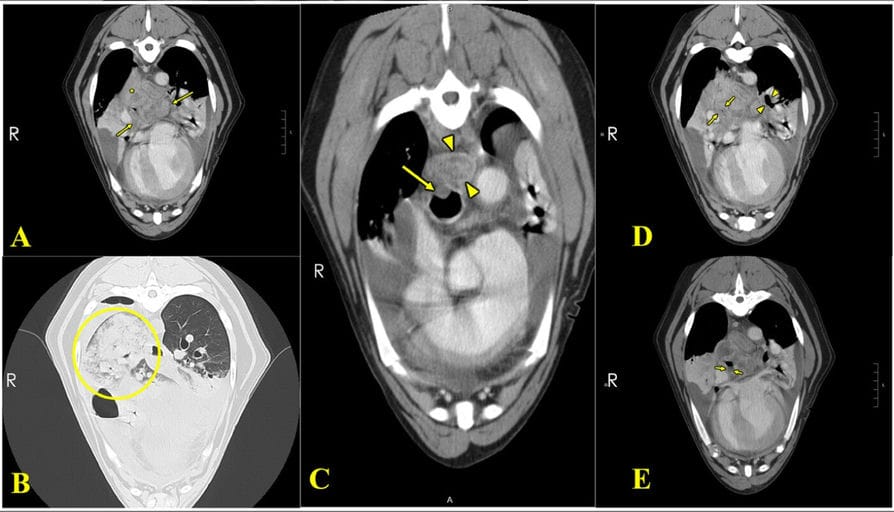

Computed tomography (CT) images of a canine thoracic cavity of a dog with fibrosing mediastinitis. In image A, an axial CT image reveals a heterogeneously enhancing mass within the right caudal lung lobe (yellow asterisk), adjacent to an enlarged middle tracheobronchial lymph node (between arrows). In image B, an axial view of the right caudal lung lobe displays a dense alveolar pattern (yellow circle). Image C shows esophageal thickening (between arrowheads) and moderate thickening of the dorsal tracheal membrane (arrow). Image D, there is marked narrowing of the right caudal lung lobe bronchus with significant peribronchial and bronchial soft tissue thickening and rim enhancement (between arrows), while the left caudal lung lobe bronchus is less severely affected (between arrowheads). Image E demonstrates fluid within the right caudal lung lobe bronchus (between arrows).

Imaging revealed pleural effusion, a mediastinal mass-like structure compressing the trachea, oesophagus, and pulmonary veins, and enlarged tracheobronchial lymph nodes. Cytology showed pyogranulomatous inflammation without infectious organisms. Despite antimicrobial therapy and oxygen support, the dog’s condition deteriorated, with worsening facial edema and dysphagia. Euthanasia was elected due to poor prognosis. Necropsy identified a large fibrotic mediastinal mass with severe chronic granulomatous inflammation, vasculitis, and fibrosis consistent with fibrosing mediastinitis. No infectious agents were detected on histopathology or special stains.